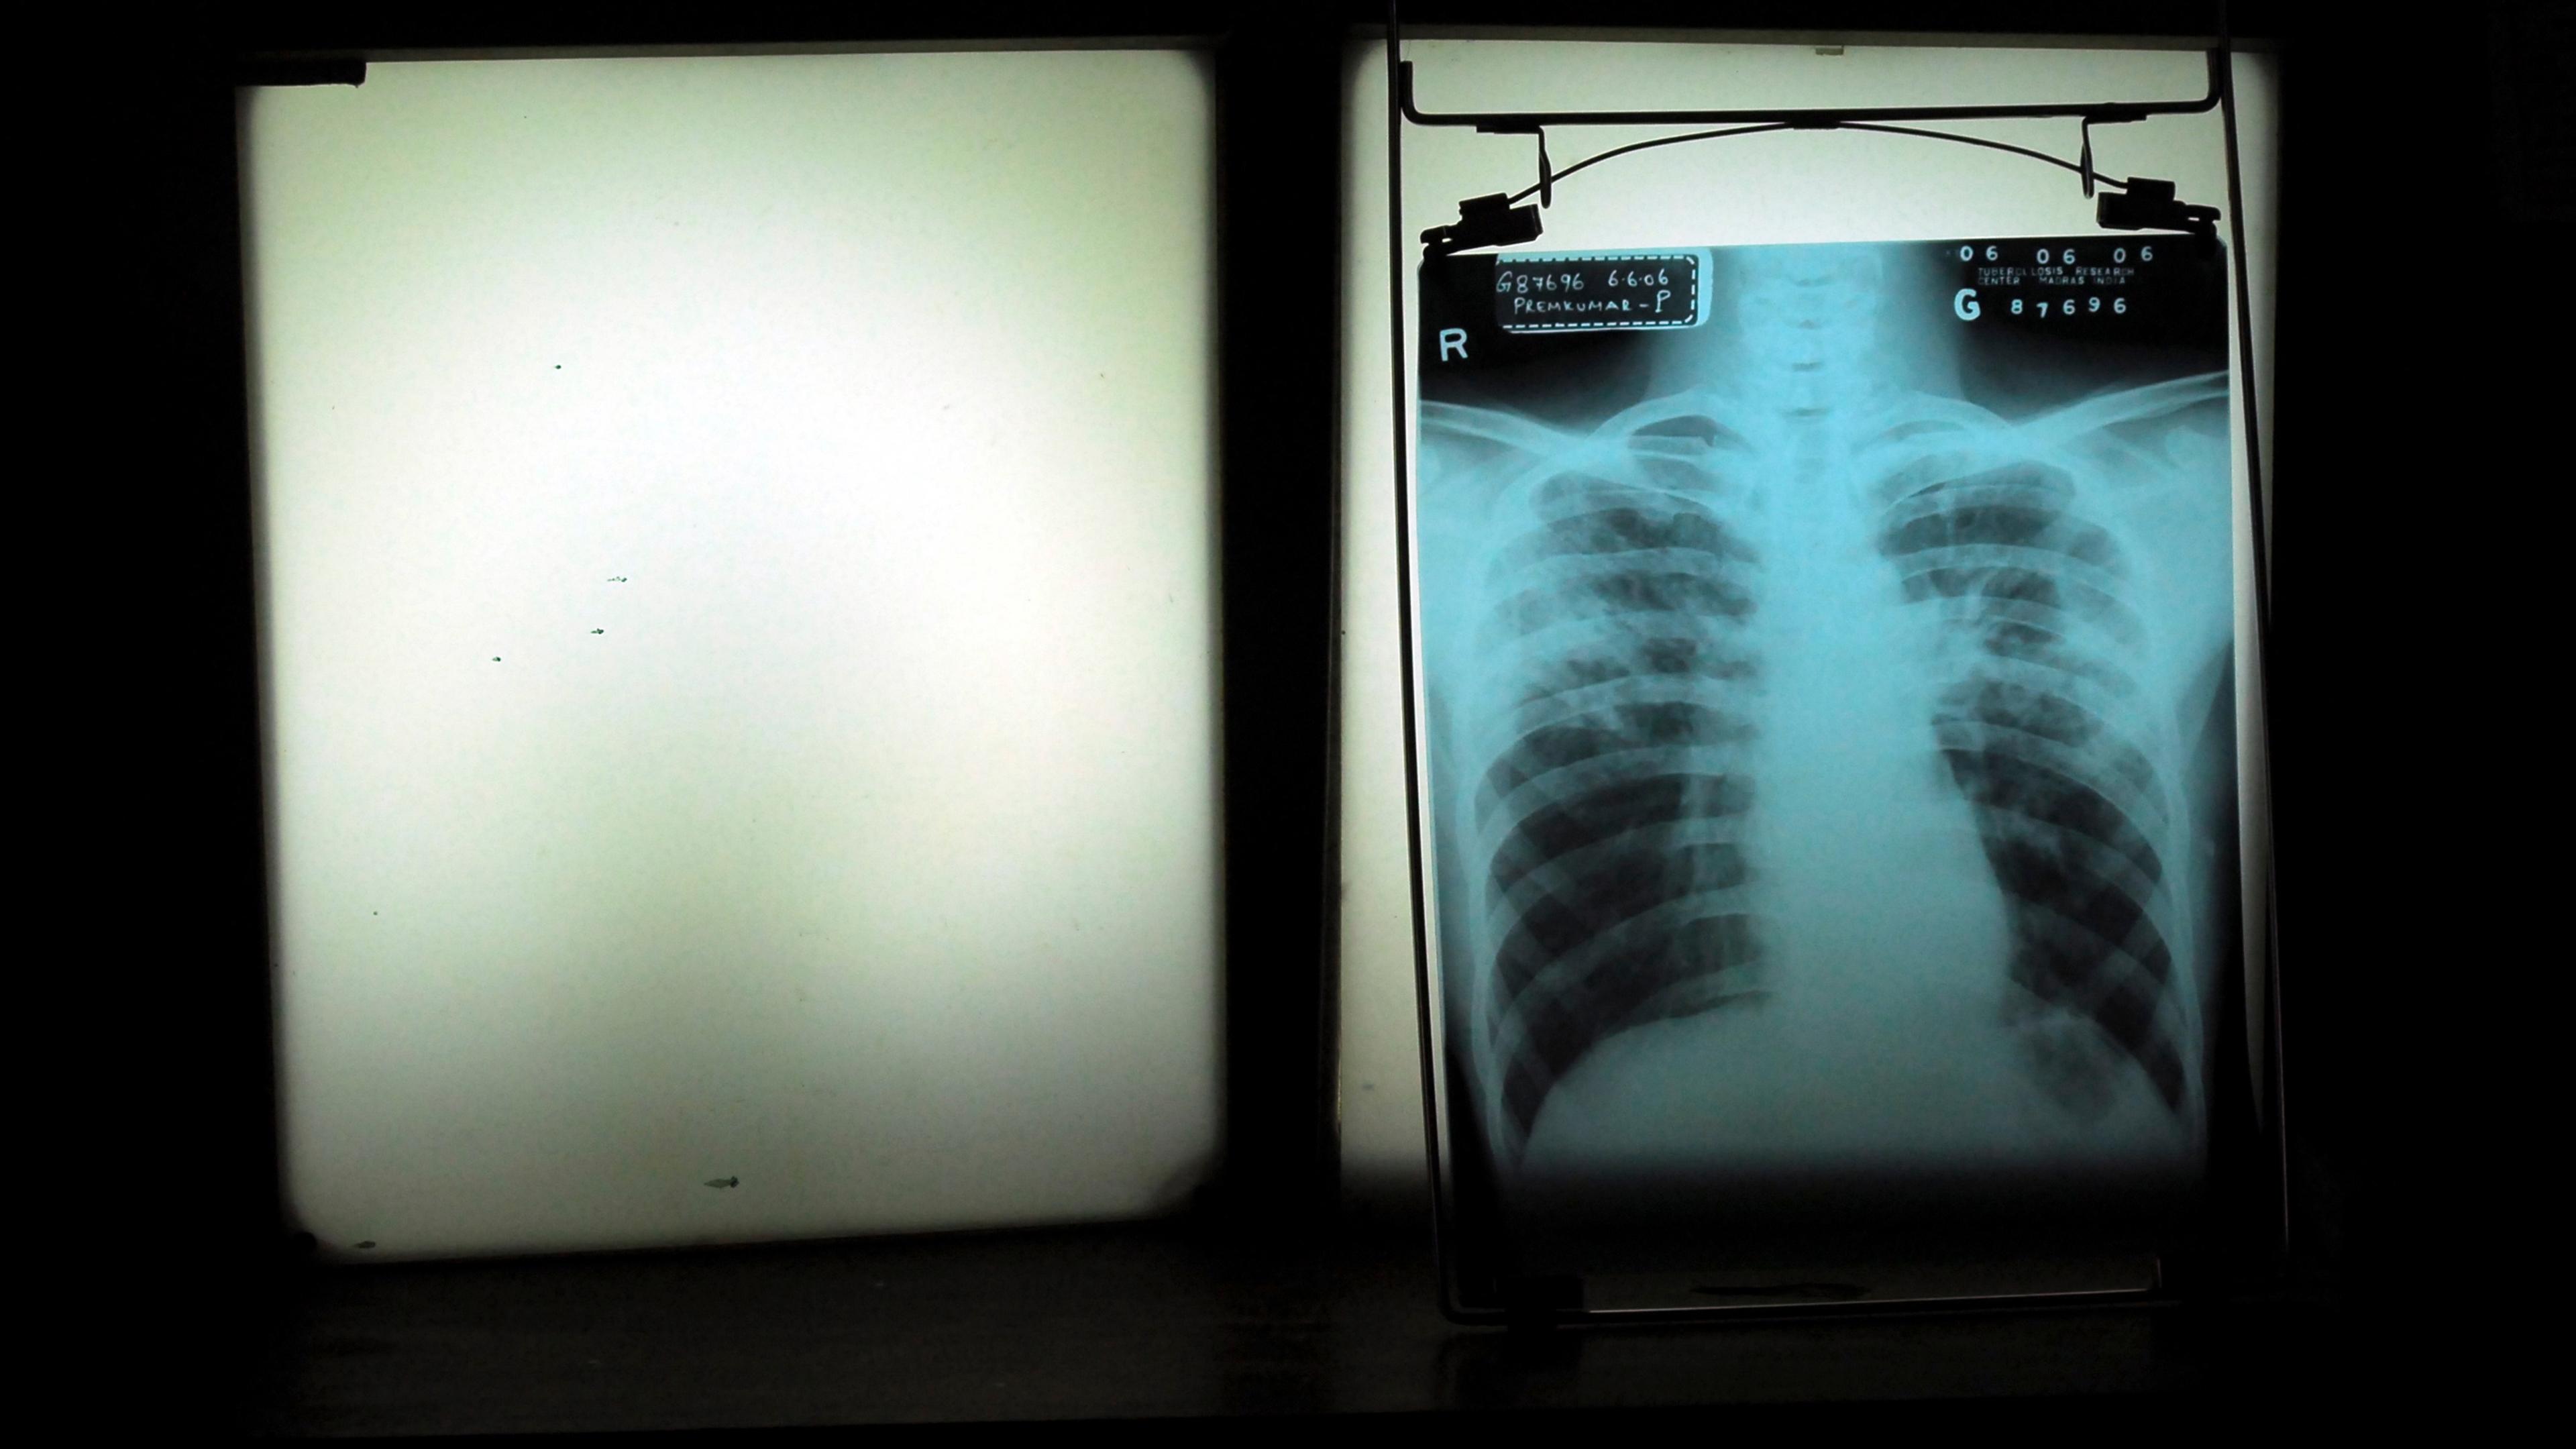

Some of these tuberculosis patients were cured – at least, for a while. But weeks, months, even years later, former patients would return, coughing, to face another diagnosis of tuberculosis, and another round of antibiotic treatment. Across the various hospitals and clinics where I conducted fieldwork, I heard patients insist to their doctors that they had taken their medications as directed, and that they had been declared cured. Many of them even had paperwork – old X-rays, prescriptions and medical charts – attesting to these prior rounds of treatment. Despite the failure of their previous cures to stick, these patients and their families remained optimistic that, this time, things would be different. This time, they hoped, they would be cured once and for all.